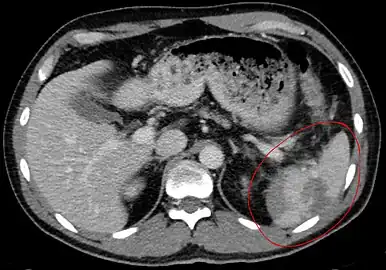

- Image of abdomen shows ruptured spleen (and the perisplenic hematoma)

- Traumatic rupture of the spleen on contrast enhanced axial CT (portal venous phase)

- Splenic hematoma resulting in free abdominal blood

Splenic rupture is usually evaluated by FAST ultrasound of the abdomen.[3] Generally this is not specific to splenic injury; however, it is useful to determine the presence of free floating blood in the peritoneum.[3] A diagnostic peritoneal lavage, while not ideal, may be used to evaluate the presence of internal bleeding a person who is hemodynamically unstable.[4] The FAST exam typically serves to evaluate the need to perform a CT scan.[4] Computed tomography with IV contrast is the preferred imaging study as it can provide high quality images of the full peritoneal cavity.[3]